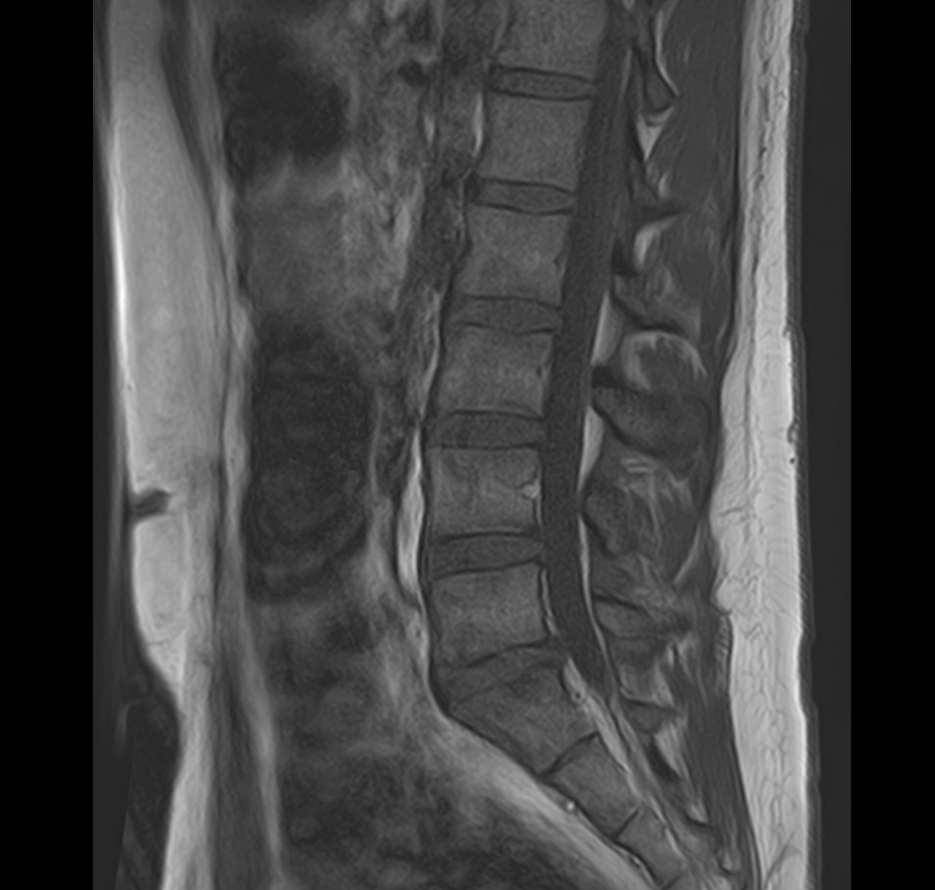

Боль в нижней части спины является наиболее распространенным симптомом различных заболеваний позвоночника, которые поражают пояснично-крестцовый отдел. В ряде случаев боли в нижних отделах спины сочетаются с кокцигодинией, то есть болями в рудиментарной части позвоночного столба – копчике. Причинами появления таких симптомов могут быть воспалительные процессы, дегенеративно-дистрофические заболевания позвоночника, опухолевые поражения данной анатомической области.

МРТ является наиболее информативным способом диагностики заболеваний позвоночника, так как позволяет оценить состояние костных структур позвонков, расположенную здесь часть спинного мозга с нервными корешками, а также связки, сухожилия и окружающие мягкие ткани. Магнитно-резонансная томография превосходит все другие методы диагностики не только по информативности, но и по безопасности, так как в основе метода лежит использование внешнего магнитного поля и отсутствует вредное для организма воздействие облучения, свойственное рентгену.

Для выявления причин появления кокцигодинии и болей в нижней части спины в клинике «Доступная медицина» проводится комплексное обследование МРТ пояснично-крестцового отдела + копчик, включающее два протокола исследования каждой анатомической области.